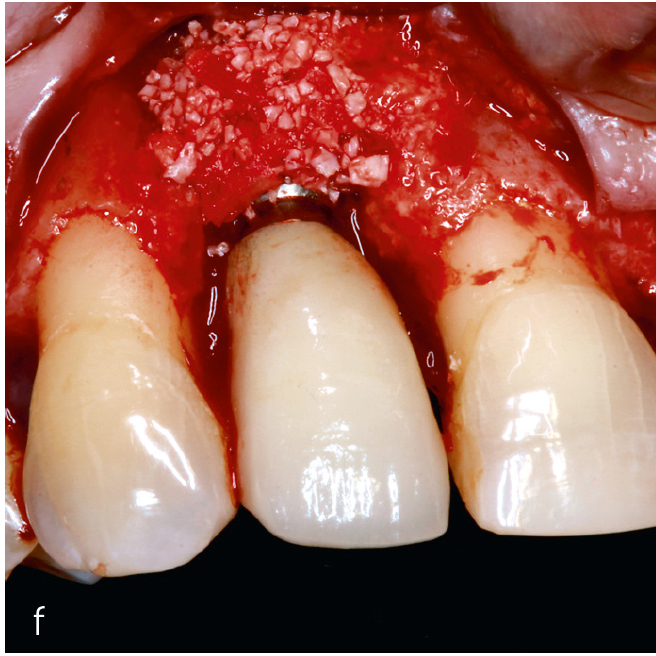

Die kombinierte chirurgische Periimplantitstherapie ist bei fortgeschrittenen Knochendefekten mit komplexer Morphologie indiziert64 (Abb. 3). Die Kombination augmentativer Verfahren mit der Implantoplastik, die am suprakrestalen Implantatanteil vorgenommen wird, zeigt nach einem Beobachtungszeitraum von 7 Jahren eine hohe Effektivität48,65.

Abb. 3a bis h Falldokumentation mit Zustand nach Implantation und lateraler Augmentation alio loco: a) klinische Ausgangssituation mit Fistelung vestibulär in der Region 12; b) klinische Parameter (PI=Plaque Index 1-3, ST=Sondierungstiefe, MR=Mukosarezession, KM=keratinisierte Mukosa, BOP=Bleeding on probing, SUPP=Suppuration); c) radiologische Ausgangssituation mit initialem periimplantären Knochenabbau; d) operativer Zugang; e) Defektdarstellung nach Entfernung des periimplantären Entzündungsgewebes; f) Defektaugmentation mit einem Gemisch aus Eigenknochen und xenogenem Knochenersatzmaterial; g) Kollagenmembran; h) das aus dem Gaumenbereich entnommene Bindegewebstransplantat (BGT).